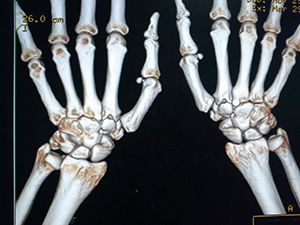

КТ лучезапястного сустава представляет собой диагностическое исследование кисти, которое выполняется на современном рентгеновском оборудовании — мультиспиральном компьютерном томографе. В отличие от рентгенографических исследований, КТ лучезапястного сустава позволяет выявить патологию уже на ранних стадиях развития.

Протокол КТ лучезапястного сустава содержит в себе сведения, позволяющие лечащему врачу изучить в подробностях даже самые мелкие структуры, поставить диагноз и назначить соответствующее лечение. При необходимости процедура может проводиться с применением контрастного йодсодержащего вещества.